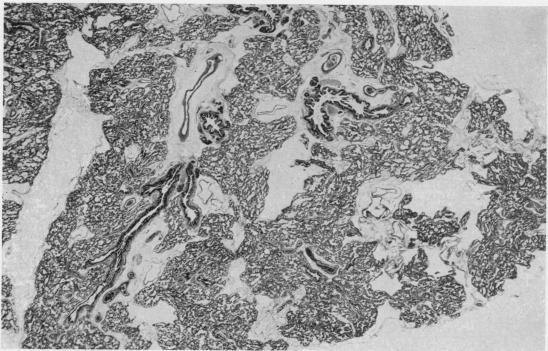

Congenital pulmonary lymphangiectasis.

J Clin Pathol. 1959 Jan;12(1):62-9. doi: 10.1136/jcp.12.1.62.